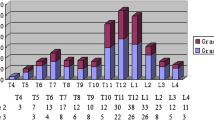

The distribution of the fractures over the individual vertebral levels showed the well-known dual-peak distribution with a peak at T7 (119 fractures, 13% of total) and at T12 (169 fractures, 18% of total) (Fig. 2). The severity of the fractures was “mild” in 458 (48% of all fractures), “moderate” in 295 (31%), and “severe” in 201 (21%). Vertebral fractures were wedge shaped in 79% (n = 759), biconcave in 19% (n = 178) and “crush” in 2% (n = 17). Mild fractures were often accompanied by moderate or severe fractures, and on a per patient analysis 219 patients (9% of all patients) had mild fractures only.